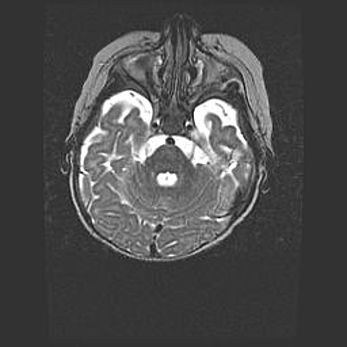

Подострая гематома правой гемисферы мозжечка.

Наружная гидроцефалия.

Возраст: 15 дней

Вес: 3100 г

Пол: женский

Окружность головы: 37 см

Срок гестации: 35-36 недель

При открытой наружной форме гидроцефалии у новорожденных расширяются и переполняются субарахноидные пространства.

Кровоизлияния в мозжечок имеют две клинико-анатомические формы: полушарные гематомы и кровоизлияния в червь.

К появлению этой патологии может привести: повреждения головного мозга, возникающие в результате асфиксии и гипоксии плода при беременности, или травмы во время родов. Редко гематома мозжечка может быть результатом первичной коагулопатии и сосудистой мальформации, диссеминированном внутрисосудистом свертывании, изоиммунной тромбоцитопении.